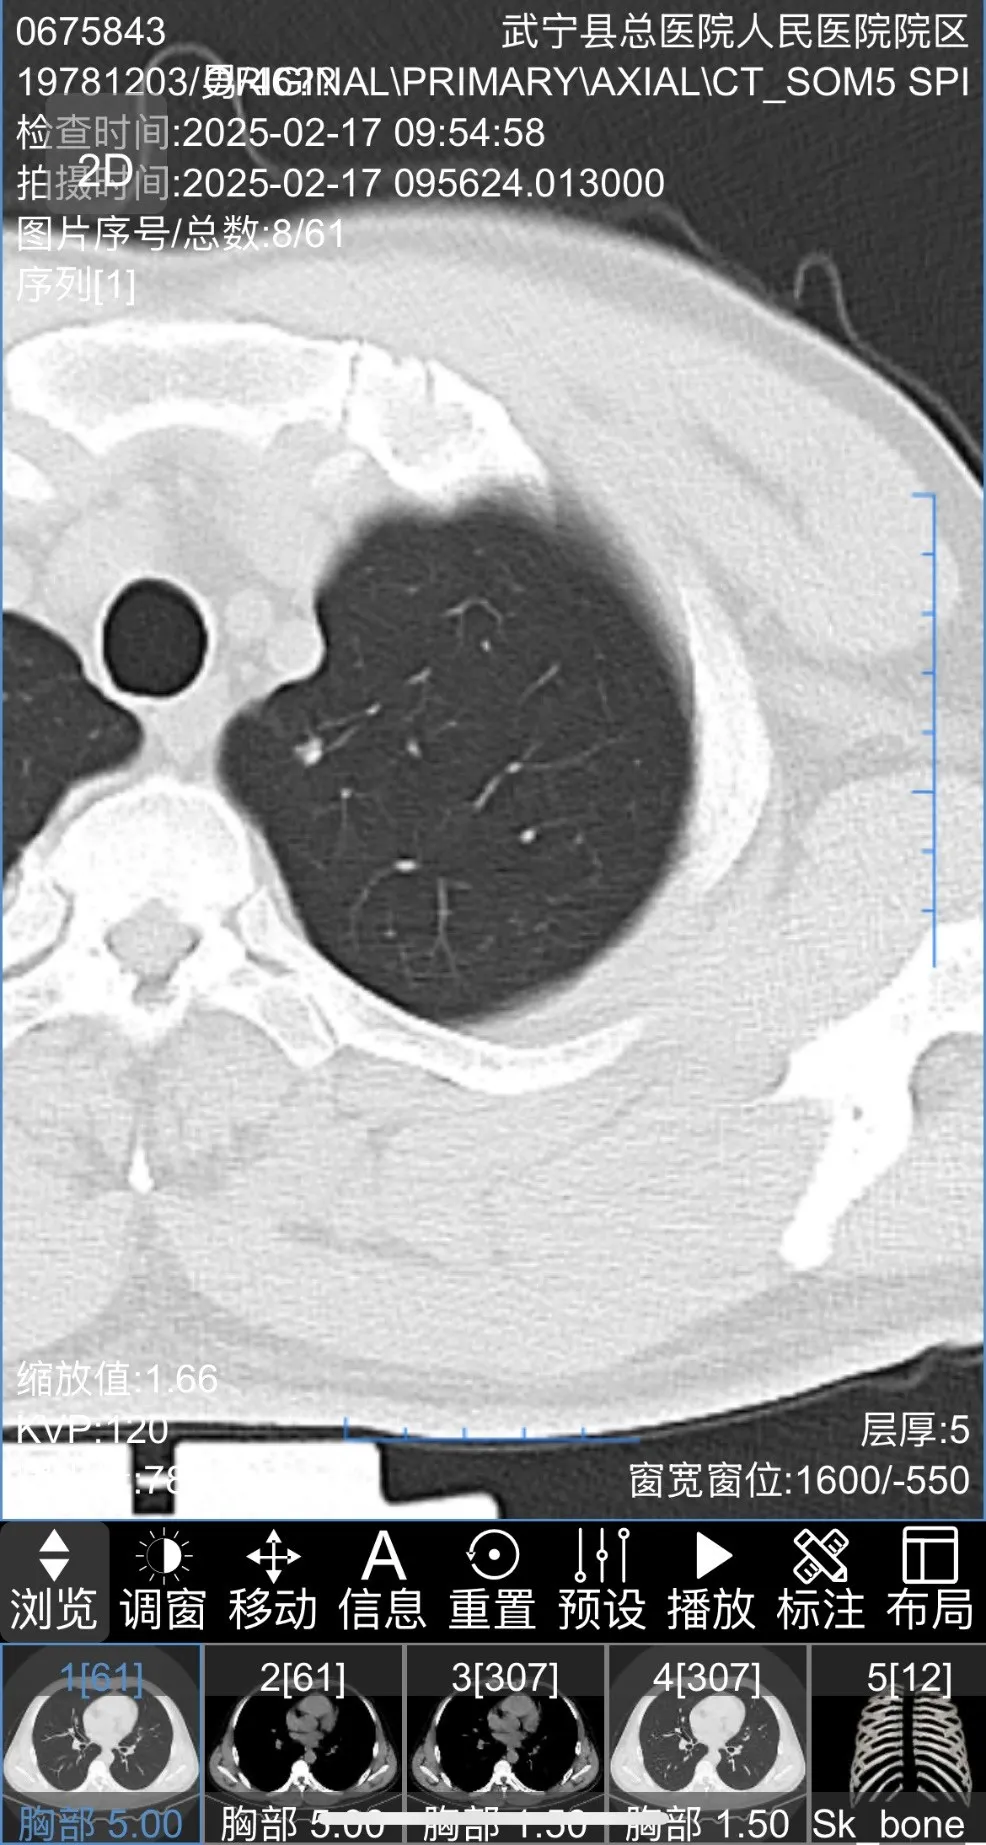

患者胸部(bù)CT圖片如下

三維重建後圖片如下